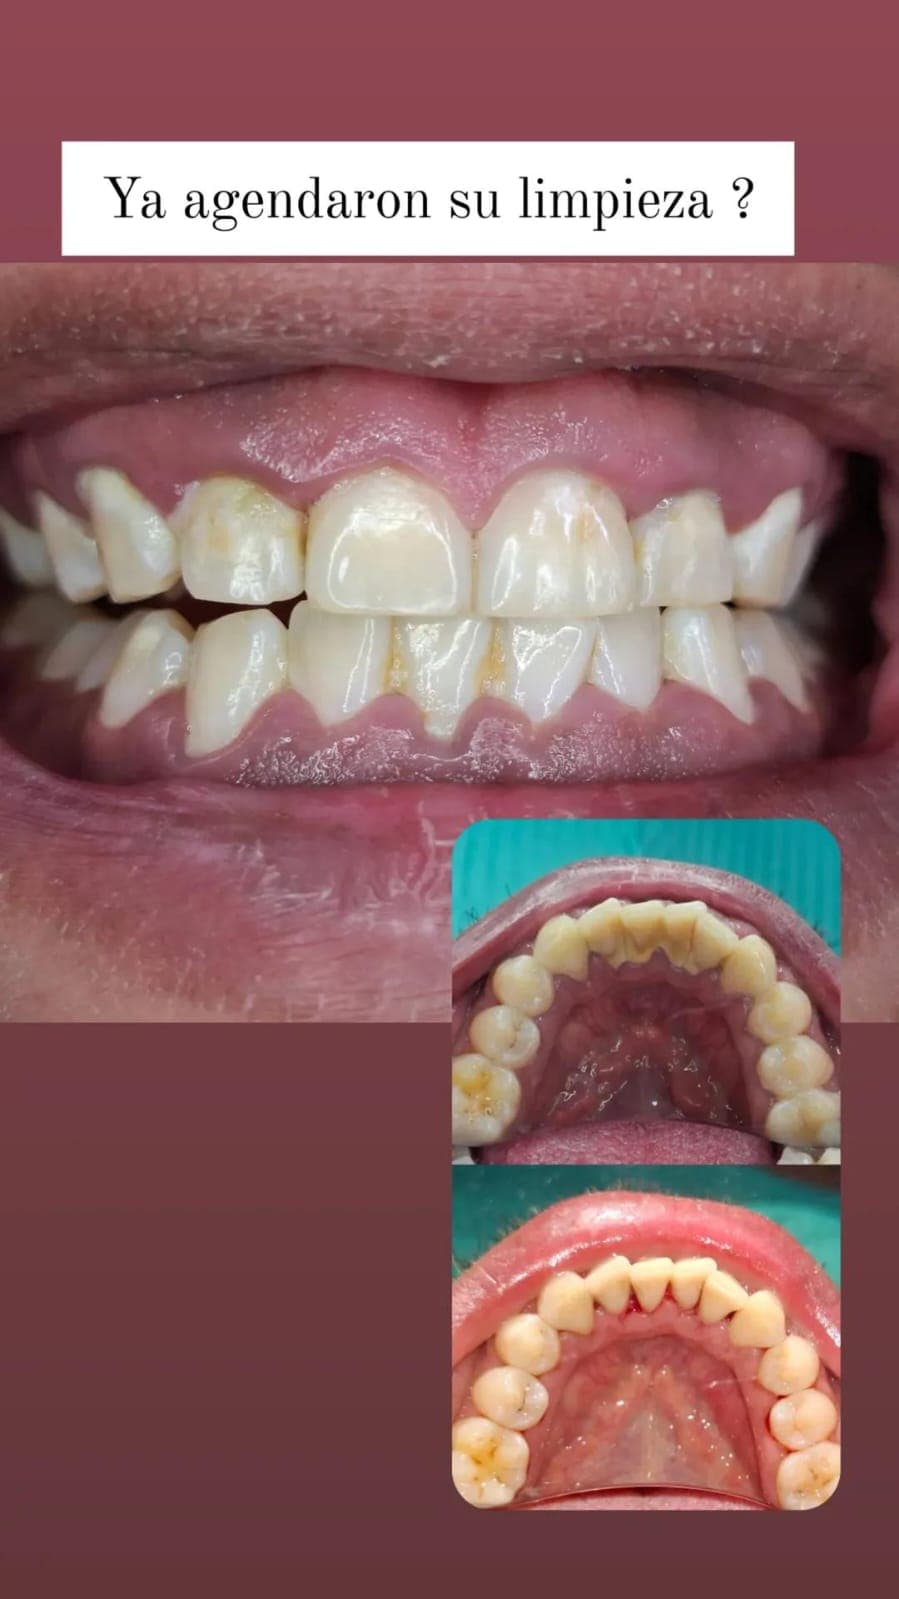

Eliminación de sarro y placa para prevenir caries y enfermedades gingivales.

Conoce algunos de los tratamientos realizados en nuestra clínica. Excelencia y dedicación en cada sonrisa.